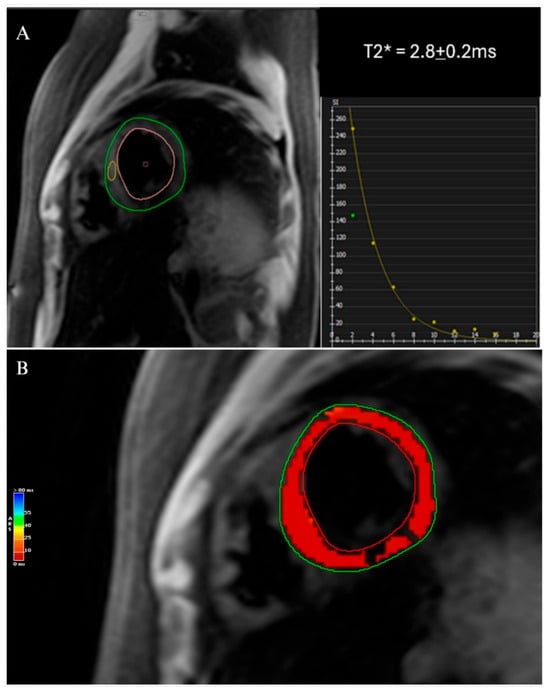

| Cardiac Magnetic Resonance (CMR): T2* Mapping and Quantification [19,50,79,82,83] | Decreased T2* signal, myocardial iron deposition, LV dysfunction | High sensitivity and specificity, non-invasive, quantifies iron load, excellent tissue characterization, proven when guiding therapy to improve outcomes | Expensive, limited availability, requires breath holding, contraindicated in patients with certain implants |

| T1 Mapping [83,84,85] | Low T1 values indicating iron overload | Non-invasive, high diagnostic accuracy, differentiates severity, reproducible | Requires specialized software, less widely available, variability between scanners |

| T2 Mapping [83,84,85] | Low T2 values indicating iron overload; T2 < 20 ms* indicating presence of myocardial iron overload, <10 ms* associated with high risk of heart failure; <6 ms* indicating severe myocardial iron overload | Non-invasive, high diagnostic accuracy, differentiates severity, reproducible | Requires specialized software, less widely available, variability between scanners |